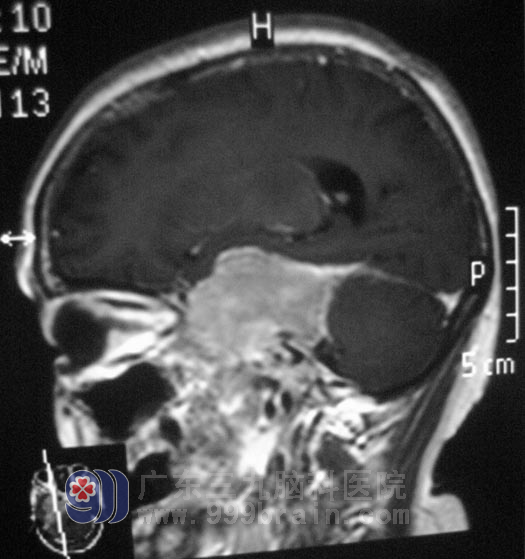

60岁的刘女士,六年前无明显诱因出现右侧肢体乏力,以上肢为甚,进行性加重,以为是风湿、疲劳引起,也就没有去医院进行治疗。一年多前开始出现吞咽困难,并且症状逐渐加重,同时伴有视物模糊,服用多种药物治疗,效果欠佳。今年2月去当地医院行头部MRI检查,提示“右侧鞍旁巨大占位性病变,大小约52.5mm×8mm×64.1mm”,原来这就是折腾了刘女士6年的病根:

入住广东三九脑科医院时,刘女士精神差,睁眼乏力,言语表达不清,嘴角稍向右偏,鼓气动作乏力。发音嘶哑、饮水呛咳、吞咽困难,悬雍垂右偏,咽反射迟钝,右侧肢体肌力III级,综合神经外科 鲁明主任详细了解病史后,结合影像资料初步考虑为脑膜瘤。7月13日,由鲁明主任主刀,在全麻下行经颞部颞下入路行鞍旁占位性病变切除术,术中见肿瘤位于右侧前中后颅窝,侵犯硬脑膜并破坏颅底骨质,范围广,内侧至海绵窦、鞍区、脑干,后至小脑幕,下至前中后颅窝底,用超声刀及双极电凝逐步切除肿瘤,海绵窦区及脑干区小部分肿瘤粘连较紧。手术后,刘女士顺利渡过水肿期、感染期,下一步就是进行康复治疗。术后经病理证实为:(右侧鞍旁)脑膜瘤,WHO I级。